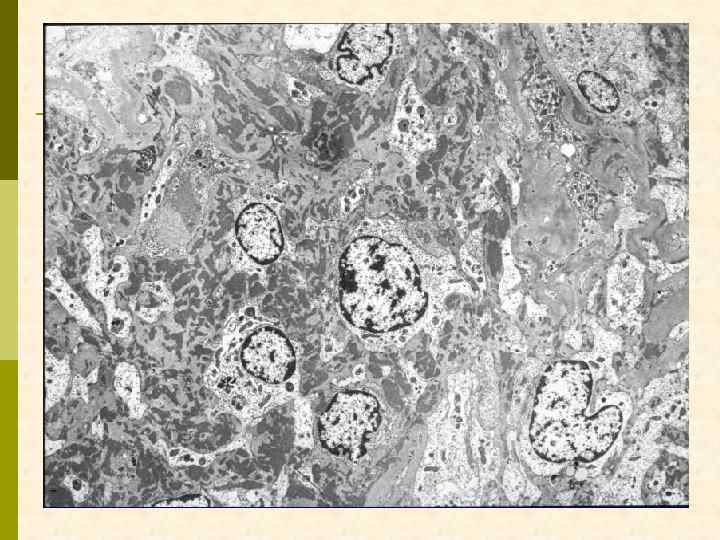

Мембрано-пролиферативный гломерулонефрит (DDD)

DDD – болезнь плотных депозитов (мембрано-пролиферативный гломерулонефрит II типа) q DDD – системная болезнь неизвестного происхождения q Клиническая характеристика q мебрано-пролиферативный гломерулонефрит q С 3 при ИФИ, без отложений иммуноглобулинов q поражение глаз q депозиты в капиллярах сетчатки, мембране Bruch q парциальная липодистрофия q хроническая гипокомплементемия, высокая подверженность инфекциям q высокая частота сахарного диабета